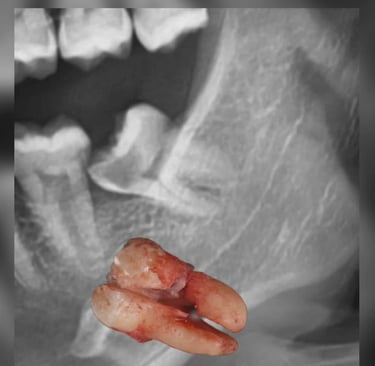

If you've ever had a wisdom tooth that just won't stop aching, or you've been told your tooth is "impacted," chances are you've heard about Minor Oral Surgery (MOS). While the name might sound intimidating, MOS is actually a straightforward and commonly performed dental procedure — and at Lau Dental Clinic & Surgery, we make the experience as smooth and stress-free as possible.

Minor Oral Surgery involves small surgical procedures done inside the mouth, often under local anaesthesia. The most common reason patients need MOS is to remove impacted or partially erupted wisdom teeth. However, it’s also used for removing broken tooth roots, treating dental cysts, or even preparing the mouth for dentures or implants. Unlike major surgery, MOS is minimally invasive, doesn’t require general anaesthesia, and is usually completed in under two hours.

Once you're comfortable and the area is numb, our experienced dentist gently makes a small incision to access the tooth or problem area. Depending on the complexity, the tooth may be removed whole or in smaller sections. The site is then cleaned and stitched if necessary. Most MOS procedures here take only about 1 to 1.5 hours, and patients are often surprised by how quick and painless it feels.